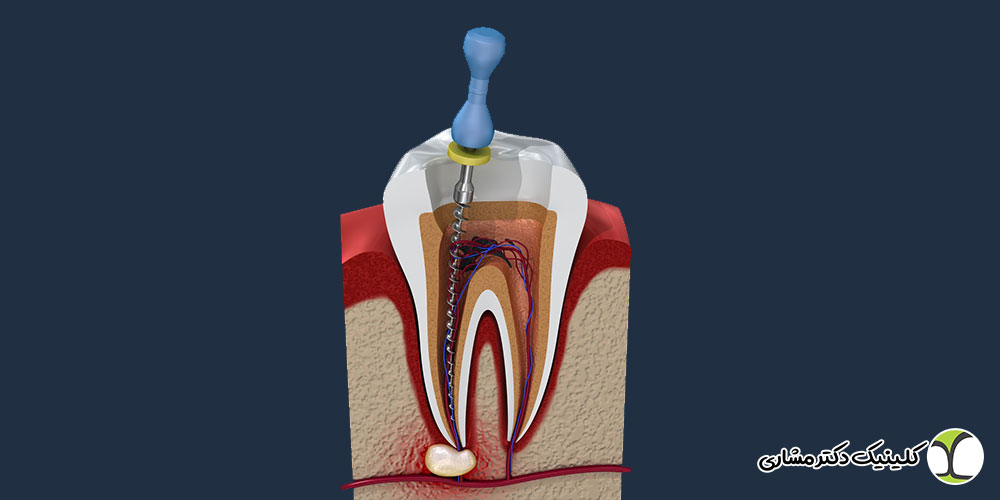

عصب کشی دندان در پاسداران چگونه انجام میشود؟

عصب کشی دندان در پاسداران – درد دندان یکی از دردهایی است که اکثر افراد حداقل یک بار در زندگی آن را تجربه کرده اند. گاهی این درد به قدری شدید و اذیت کننده می شود که هیچ مسکنی آن را آرام نمی کند و تنها راه، عصب کشی است. عصب کشی یک روش درمانی است […]